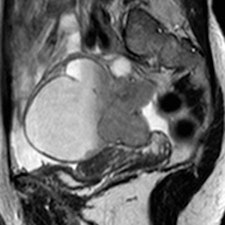

- Hereditary breast-ovarian cancer syndrome is mainly associated with ovarian high-grade serous carcinomas, which seem to arise in the fallopian fimbriae and have better prognosis than sporadic cancers.

- Lynch syndrome predisposes a patient to endometrial cancer, at a lower rate than ovarian cancers. Endometrial cancers show a predilection for the lower uterine segment and tend to be histologically more diverse in contrast to their sporadic counterparts, including nonendometrioid carcinomas. Ovarian cancers related to Lynch syndrome and Cowden syndrome are mostly of the nonserous type, usually endometrioid.